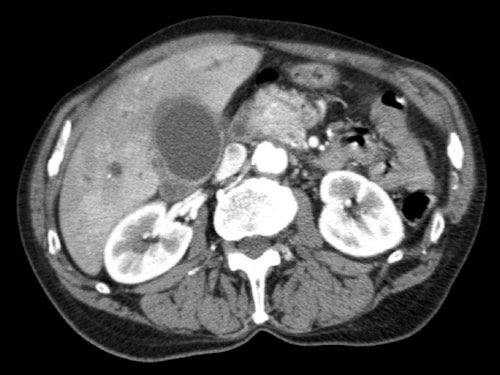

Tái tạo mặt phẳng coronal cho thấy:

- Bất thường bờ viền thành SMV được nhận thấy rõ hơn trên tái tạo coronal này (mũi tên).

- Khối u ở thân tụy (đầu mũi tên trắng).

- Huyết khối trong các nhánh bên của SMV (mũi tên xanh nhỏ).